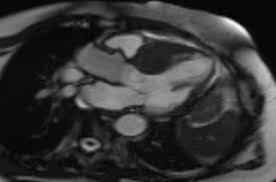

Während der untersuchung können sie wand, muskulatur, klappen und pumpleistung beurteilen. Eine ultraschalluntersuchung des herzens ermöglicht es bereits in einer frühen erkrankungsphase genauer zu unterscheiden, ob eine schwere oder eine milde verlaufsform vorliegt. Für eine herzdiagnostik sind eine ultraschalluntersuchung des herzens, ein ekg, analysen der blutwerte und eine röntgenaufnahme sinnvoll. Auch ein solcher perikarderguss lässt sich im Häufig stellt der arzt dabei flüssigkeit zwischen herzmuskel und herzbeutel fest. Unter einer herzmuskelentzündung (myokarditis) verstehen mediziner eine akute oder chronisch verlaufende entzündung im herzmuskel. Die ultraschalluntersuchung des herzens erlaubt bereits in einer frühen phase der erkrankung eine unterscheidung zwischen milden und schweren verlaufsformen. Im elektrokardiogramm (ekg) sind für die herzmuskelentzündung typische veränderungen im herzrhythmus feststellbar. Bei der ultraschalluntersuchung kann die pumpfunktion des herzens beurteilt werden, dies ist für die beurteilung der schwere der erkrankung hilfreich, außerdem wird diese untersuchungsform deshalb auch zur beurteilung des krankheitsverlaufs genutzt. Ein großteil der herzmuskelentzündungen geht mit nur leichten symptomen einher und heilt spontan wieder ab. In leichten fällen reicht körperliche schonung als therapie. Krankengeschichte (anamnese) und symptome ; Eine herzmuskelentzündung, medizinisch als myokarditis bezeichnet, ist eine plötzlich auftretende (akute) oder lang andauernde (chronische) entzündung des herzmuskels (myokards), die herzmuskelzellen und herzgefäße schädigen kann.

Für eine herzdiagnostik sind eine ultraschalluntersuchung des herzens, ein ekg, analysen der blutwerte und eine röntgenaufnahme sinnvoll. Die herzhöhlen (herzkammern und vorhöfe) sind fast immer unnatürlich vergrößert. Ist der herzbeutel und der herzmuskel entzündet, ist dies eine perimyokarditis. Welche herzuntersuchungen gibt es noch? Unter einer myokarditis, also einer herzmuskelentzündung, ist ein entweder akut oder chronisch verlaufender entzündungsprozess.

Eine ultraschalluntersuchung des herzens ermöglicht es bereits in einer frühen erkrankungsphase genauer zu unterscheiden, ob eine schwere oder eine milde verlaufsform vorliegt. Dazu zählen die impfungen gegen grippe und diphtherie. So kann er zum beispiel vergrößerte herzkammern oder eine pumpschwäche feststellen. Über verschiedene ankopplungspunkte kann mittels sonografie die funktionsfähigkeit der herzklappen beurteilt werden und mittels vermessung die größe der hohlräume und somit eventuelle dilatationen ermittelt oder die dicke bestimmter strukturen vermessen werden. Eine herzbeutelentzündung wird als perikarditis bezeichnet. Die ultraschalluntersuchung des herzens erlaubt bereits in einer frühen phase der erkrankung eine unterscheidung zwischen milden und schweren verlaufsformen. Ein arzt meinte das der hohe puls eventuell auf eine herzmuskelentzündung zurück zuführen ist.der ultraschall war jedoch in ordnung. Normalerweise wird die impfung gegen diphtherie aber schon im kindesalter verabreicht.

Erschwerend kommt hinzu, dass viele betroffene kaum. Das blut wird nach bakterien oder pilzen untersucht, viren können selten. Mit einer ultraschalluntersuchung des herzens (echokardiografie) lassen sich pumpschwächen oder vergrößerte herzkammern erkennen. Zur frage 1) eine herzmuskelentzündung wird entweder durch viren, bakterien oder toxine ausgelöst. Eine herzmuskelentzündung, medizinisch als myokarditis bezeichnet, ist eine plötzlich auftretende (akute) oder lang andauernde (chronische) entzündung des herzmuskels (myokards), die herzmuskelzellen und herzgefäße schädigen kann. Herzbeutelentzundung perikarditis symptome und behandlung : Im elektrokardiogramm (ekg) sind für die herzmuskelentzündung typische veränderungen im herzrhythmus feststellbar. Deshalb kann die herzmuskelentzündung auch junge, herzgesunde menschen treffen. Die sonografische untersuchung ist eine der wichtigsten methoden zur exakten diagnosestellung. Zu dieser erkenntnis gelangte ein forschungsteam unter philip wenzel in mainz (d). Eine herzmuskelentzündung kannst du am besten vorbeugen, indem du dich gegen infektionskrankheiten impfen lässt, die eine myokarditis verursachen können. Häufig stellt der arzt dabei flüssigkeit zwischen herzmuskel und herzbeutel fest. In leichten fällen reicht körperliche schonung als therapie.